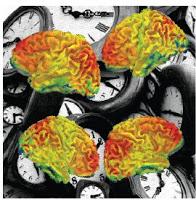

El estudio, publicado

en la revista eLife, muestra que las áreas sensoriales del cerebro que reciben

información de escalas temporales neuronales intrínseca está alterado en el

autismo. Las imágenes de resonancia magnética de los cerebros de adultos

varones con autismo de alto funcionamiento se compararon con las de personas

sin autismo. En el estado de reposo, ambos grupos mostraron el patrón esperado

de escalas de tiempo más largas en áreas del cerebro frontal relacionadas con

el control ejecutivo, y escalas de tiempo más cortas en áreas sensoriales y

motoras. Encontraron respuestas

neuronales más sensibles en aquellos individuos con los síntomas autistas más

severos. Un área del cerebro que mostraba el patrón opuesto era el caudado

correcto, donde la escala de tiempo neural era más larga de lo normal,

particularmente en individuos con conductas más repetitivas y restringidas más

severas. Estas diferencias en la actividad cerebral también se encontraron en

exploraciones separadas de niños autistas y neurotípicos. El equipo de

investigadores japoneses y del Reino Unido piensa que los cambios estructurales

en pequeñas partes del cerebro vinculan estas dinámicas locales con los

síntomas de TEA. Encontraron cambios en el volumen de materia gris en las áreas

con escalas de tiempo neuronales atípicas. Una mayor densidad de neuronas puede

contribuir a los patrones de actividad neuronal repetitiva y recurrente, que

subyacen a las escalas de tiempo más largas y más cortas observadas en el

caudado derecho y las cortezas sensoriales y visuales bilaterales,

respectivamente. Esto puede explicar una característica prominente del autismo,

el gran peso dado por el cerebro a la información sensorial local y la

hipersensibilidad perceptiva resultante.